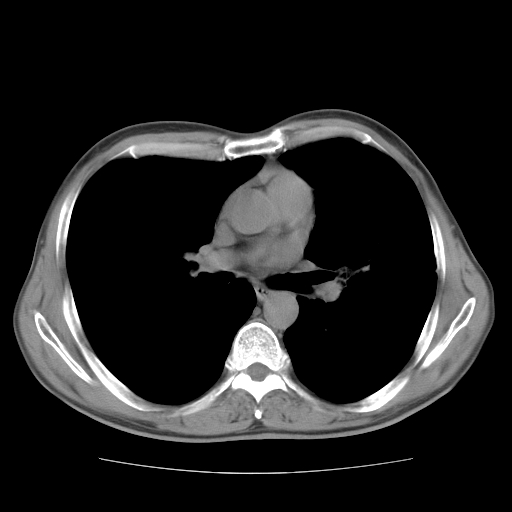

以下是引用drzhang8888在2008-11-20 22:20:00的发言:[br]密集的短毛刺,血管集束,胸膜凹陷,周边型肺癌可能性大,另双肺多发磨玻璃影,考虑感染

以下是引用流浪星在2008-11-20 22:28:00的发言:[br]左肺上叶近外围区见一类圆形结节影,毛刺征、胸膜尾征阳性,临近肺组织见多发渗出灶。考虑1,炎症性病变。 2.周围性肺癌。建议抗炎治疗后复查。

以下是引用qc80012345在2008-11-21 5:53:00的发言:[br]支持;周围型肺癌诊断。增强扫描。